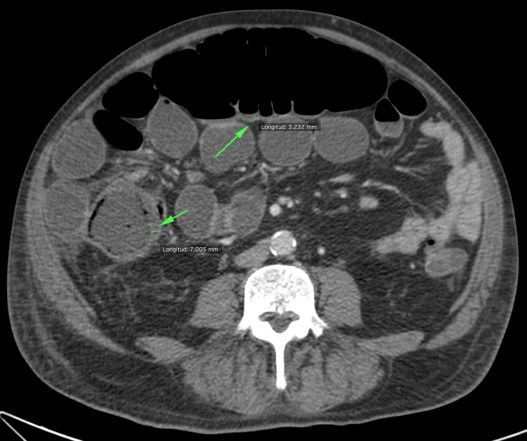

Se realiza TC de abdomen en vacío y con contraste en fase portal:

Estamos ante un cuadro de isquemia intestinal en un paciente con bajo gasto cardiaco con afectación principal de asas intestino delgado, territorio vacularizado por la arteria mesentérica superior.

5º) Neumatosis intestinal y portal. Aire extraluminal.

Son signos poco frecuentes pero muy específicos de isquemia intestinal, E cercana al 100%. Se obsevan mejor en el TC SIN contraste.

La neumatosis intestinal consiste en aire localizado en la pared del intestino. Se produce por discontinuidad de la pared con paso de aire hacia las capas más externas y a las venas intramurales.

La presencia de neumatosis portal y mesentérica consiste en pequeñas burbujas de gas dentro de los vasos mesentéricos o que también pueden extenderse hacia las ramas intrahepáticas de la vena porta, encontrándose típicamente en la periferia del hígado.